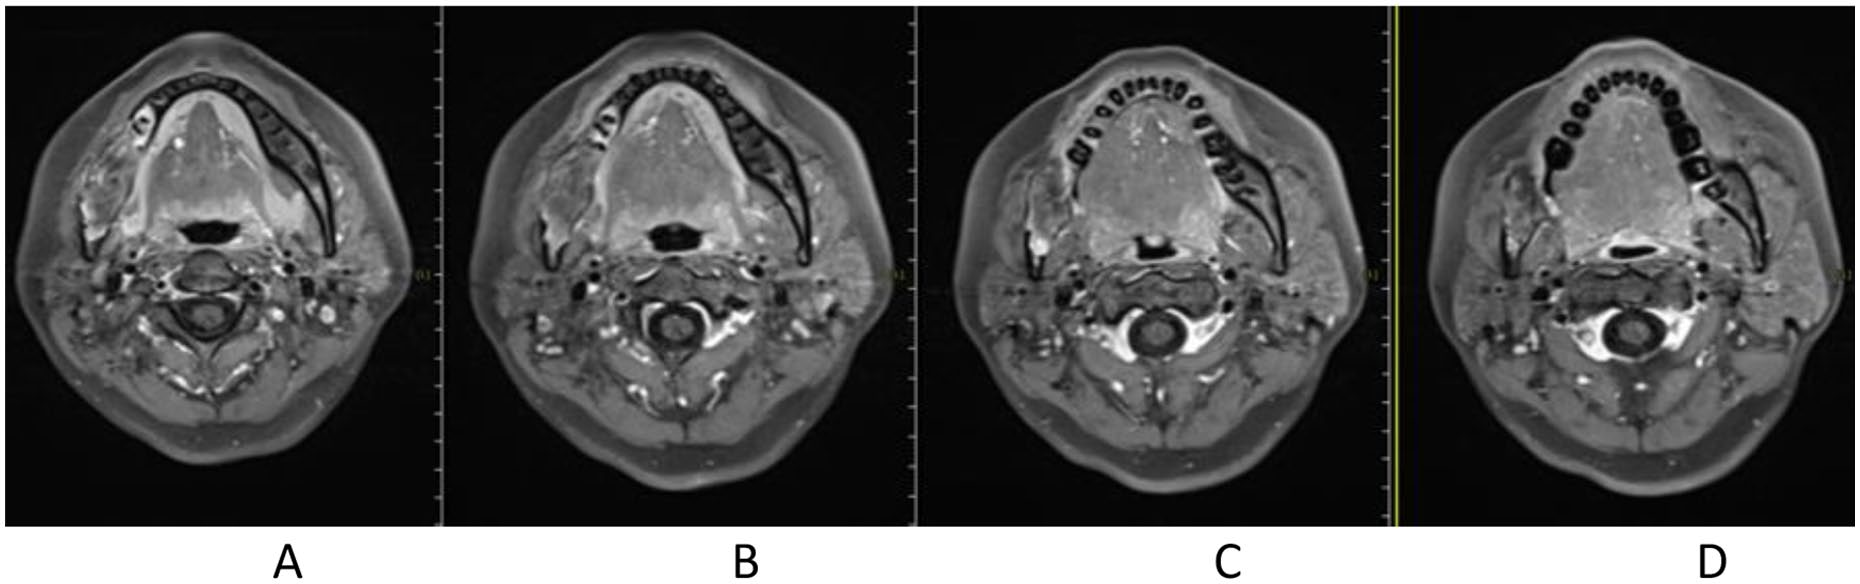

Figure 3. Before CIRT (2020-04) different slices of Contrast-enhanced MR T1: A. Contrast-enhanced MR T1, B. Contrast-enhanced MRI, TWI1, C. Contrast-enhanced MR T1, D. Contrast-enhanced MR T1

Figure 4. After CIRT.

Figure 5. 1 month after CIRT.

Figure 6. 3 months after CIRT.

Treatment was tolerated well. During and after CIRT, there was only grade 2 skin (Figure 2) and oral mucosa acute adverse event, and no grade ⩾3 RTOG acute effect. During and after CIRT, her pain in the right mandible is continued but never aggravated, but painkiller is not needed; 6-month post completion of radiotherapy, she was in a very good clinical state, and the pain in the right mandible resolved completely. One to three months after CIRT, there were no significant changes of tumor size on MRI (Figures 3–6), just intensity of contract enhancement gradually diminished on contract-enhanced T1-weighted MRI; from 6months on, the size of the tumor decreased gradually (Figure 7); up to 16months after CIRT, it regressed to 3.6cm×3.2cm×1.7cm; and on 19months after CIRT, it regressed to 3.6cm×3.2cm×1.7cm, and the efficacy evaluation is PR (partial response) (Figures 8–10).